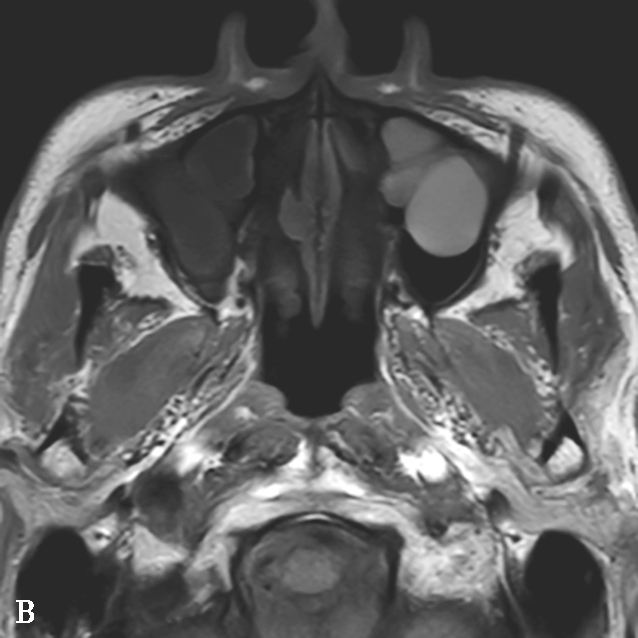

图1-3-27 鼻窦黏膜下囊肿

A.横断面T 1 WI,示左侧上颌窦多发丘状高信号病变,右侧上颌窦病变呈低信号;B.横断面T 2 WI,示双侧上颌窦病变呈高信号;C.增强后横断面T 1 WI+FS+C,示病变边缘黏膜强化,注意增强后左侧上颌窦病变并非真实强化